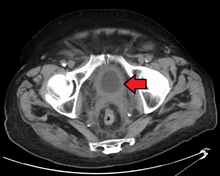

Transitional cell carcinoma of the bladder. The white in the bladder is contrast. | |